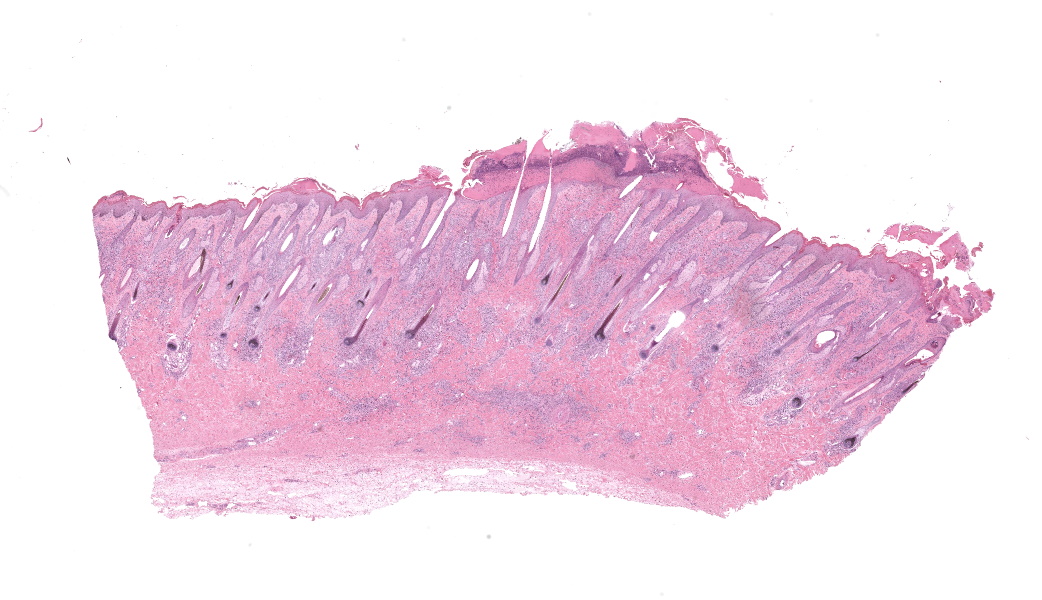

Haired skin, coronary band. Expanding and infiltrating the entire dermis are multifocal to coalescing perivascular, periadnexal and interstitial aggregates of moderate numbers of lymphocytes, eosinophils and histiocytes, fewer plasma cells and occasional neutrophils. Multifocally within dermis are few small areas of intensely eosinophilic, fragmented collagen fibers admixed with eosinophilic cellular- and basophilic nuclear debris, surrounded by epitheloid macrophages and multinucleated giant cells (eosinophilic granulomas). Intramurally and intraluminally within multiple hair follicles are moderate numbers of eosinophils, lymphocytes and histiocytes and few multinucleated giant cells (mural and luminal folliculitis), and adjacent follicular epithelium display moderate spongiosis. In the dermal-epidermal interface, there is a multifocal mild edema. The epidermis shows mild lymphocytic infiltration, mild spongiosis and occasional apoptotic keratinocyte, diffuse mild acanthosis and mild rete ridge formation (epidermal hyperplasia), moderate parakeratotic and orthokeratotic hyperkeratosis and multifocal erosions and ulcerations, the latter being covered by large serocellular crusts spanning over several adnexal units. Serocellular crusts show abundant viable and degenerated neutrophils, occasional eosinophil, cellular debris, fibrin, free keratin and hair fragments and occasional small basophilic bacterial colonies. There are also small epidermal intracorneal pustules multifocally. Several arteriolar walls in deep dermis show infiltration of few eosinophils and lymphocytes (vasculitis). The deep dermis displays mild diffuse edema.Contributor's Morphologic Diagnoses:

Haired skin, coronary band: Dermatitis and folliculitis, lymphoplasmacytic, histiocytic and eosinophilic, multifocal to coalescing, moderate, with eosinophilic granulomas, epidermal intracorneal pustules, serocellular crusts and orthokeratotic and parakeratotic hyperkeratosisEquine multisystemic eosinophilic epitheliotropic disease (MEED)